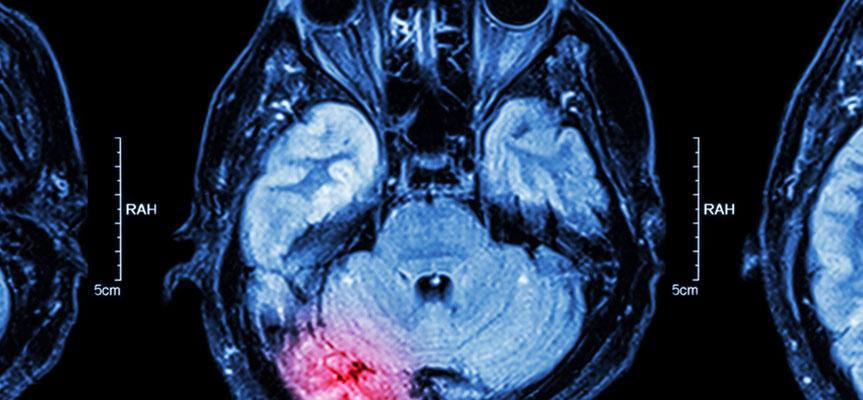

There are a wide variety of situations in which serious injuries may occur. When a person suffers an injury due to the negligence of someone else, they may be able to pursue compensation for the damages they and their family have suffered. One of the most devastating types of injuries that a person can suffer is a traumatic brain injury, which can have a long-lasting or permanent impact on someone's health and well-being. If you or your loved one have experienced brain trauma due to someone else's negligence or intentional actions, a personal injury attorney can help you determine your best options for receiving financial compensation.

There are many different situations where a person may experience a blow to the head that causes brain trauma or a medical condition that leads to brain damage. Traumatic brain injuries can have long-lasting or permanent effects on a person's life, including memory loss, problems with balance and coordination, impairments to speech or cognitive functions, mood disorders, difficulties with concentration, chronic headaches, fatigue, dizziness, or blurred vision. In some cases, brain injuries may even lead to a person's wrongful death.